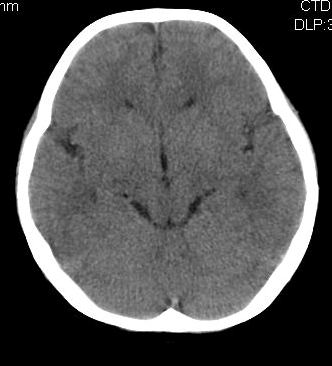

女,10岁,智力发育不良,既往史无特殊。

脑裂畸形,灰质异位